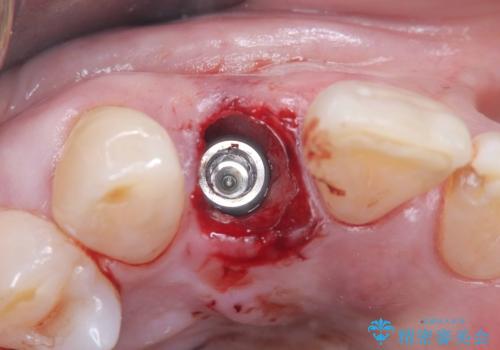

インプラント治療は、低侵襲で短期間に行える「抜歯即時インプラント治療」を選択しました。

この方法は、抜歯したその日にインプラントを埋入し、手術が1回で済むのが大きな特徴です。

治療期間も短く、抜歯からわずか3か月でオールセラミッククラウンを装着することができます。